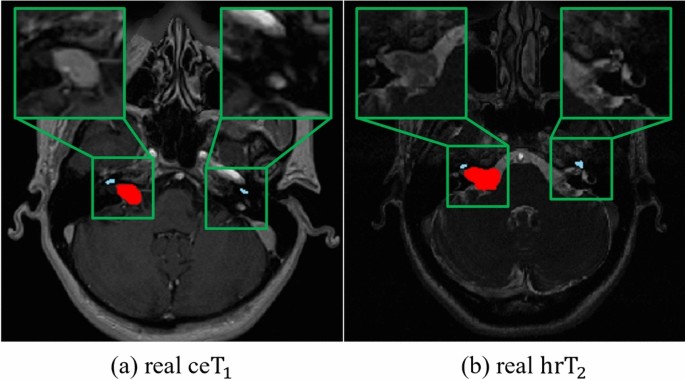

Difference in characteristics of target objects (VS and cochlea) between \(\text {ceT}_1\) and \(\text {hrT}_2\) images. (a) represents a real \(\text {ceT}_1\) image, and (b) is a real \(\text {hrT}_2\) image, with the VS highlighted in red and the cochlea in sky-blue by overlapping the segmentation map. In (a) real \(\text {ceT}_1\), the segmentation map was overlaid using the real annotation labels, while in (b) real \(\text {hrT}_2\) image, since real annotation labels were not available, we used pseudo-labels for the overlap.

Despite their success, existing methods11,12,13,14,17 do not consider the size and visual characteristics of the target object during image translation, both of which are important for successful image translation from \(\text {ceT}_1\) to \(\text {hrT}_2\). Most existing methods11,12,13, including our primary work17, have adopted instance normalization (IN)19, which performs normalization within the entire image. While IN can be effective for image synthesis tasks, it has limitations for our specific task due to the small size and distinct visual characteristics of the VS and cochlea in \(\text {ceT}_1\) and \(\text {hrT}_2\) images. In contrast to the target objects in other medical imaging datasets such as Multi-Modality Whole Heart Segmentation (MMWHS)20, the VS and cochlea in \(\text {ceT}_1\) and \(\text {hrT}_2\) are extremely small, accounting for only 0.028% and 0.002% of the total volume, respectively10. Furthermore, there are significant differences in the image characteristics of \(\text {ceT}_1\) and \(\text {hrT}_2\) for these objects. As show in Fig. 1 (a), in \(\text {ceT}_1\) images, the VS voxels appear with higher intensity compared to other tissues due to the contrast agent. Conversely, as show in Fig. 1 (b), in \(\text {hrT}_2\) images, the VS is less distinguishable from surrounding tissues since the voxels of the VS have low intensity similar to surrounding tissues1,17,21. Additionally, the cochlea, which is even smaller, appears at a very low intensity in \(\text {ceT}_1\) images (Fig. 1 (a)) compared with the \(\text {hrT}_2\) images (Fig. 1 (b))1,17,21. For these reasons, IN contains two major limitations for our task of translating \(\text {ceT}_1\) to \(\text {hrT}_2\) images. Firstly, it tends to “wash away”22 the structural information of extremely small-sized target objects such as the VS and cochlea, with the cochlea being particularly affected due to its low intensity. This “wash away” effect is a significant limitation due to the failure in generating pseudo-\(\text {hrT}_2\) images that preserve the detailed structures of the VS and cochlea. Secondly, it is challenging to reflect the low-intensity style of VS that appears in real \(\text {hrT}_2\) images. Considering the significant style differences, such as intensity, between the VS in source and target images, tailored adjustments are necessary to reflect the low-intensity style of the VS in pseudo-\(\text {hrT}_2\) images. Therefore, only applying IN without these specific adjustments can lead to a continuous presence of the high-intensity style of VS, originally observed in the source images, which is not desirable for the target images.